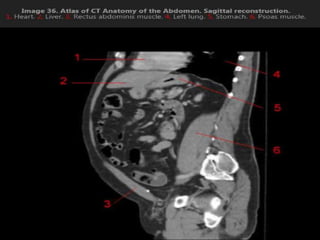

CT cross sectional anatomy.

CT – computedtomography. •Cross-sectional modality with capabilities for multiplanar reconstruction and dynamic imaging to assess vascularity •Tube rotates around the body and a circle of stationary detectors detects the penetrating x-rays forming an image.

MRI anatomy imagesof the abdomen.